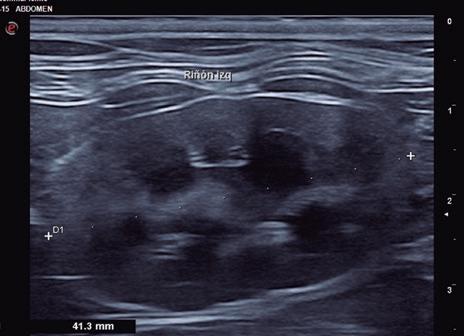

La ecografía es parte importante de los procedimientos de diagnóstico al servir para explorar la mayoría de los órganos del cuerpo. Las ondas ultrasónicas se emplean sobre todo para realizar la ecografía abdominal y la ecocardiografía. En la ecografía abdominal se explora la región abdominal junto con las venas y los ganglios linfáticos, y permite valorar alteraciones del hígado, los riñones, páncreas, y el útero, entre otros órganos. En la ecocardiografía se exploran el corazón, el pericardio y los vasos sanguíneos que llegan al corazón o salen de él.